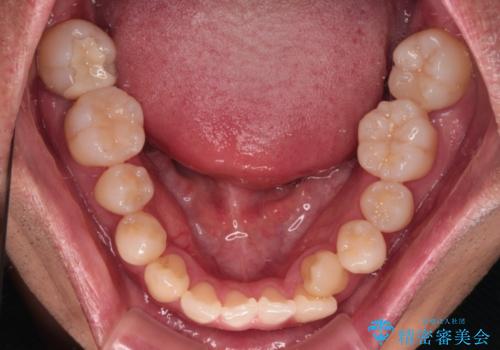

- 上下前歯部のデコボコを主訴として来院された患者様です。

上顎の歯列弓が下顎に対して狭いため、臼歯のかみ合わせがが咬頭対咬頭の状態です。

上顎の急速拡大装置を使用して、上顎骨を側方に拡大することで上顎歯列弓を拡大し、それに伴い下顎歯列弓も拡大できるようにして、歯列を整えていくこととしました。